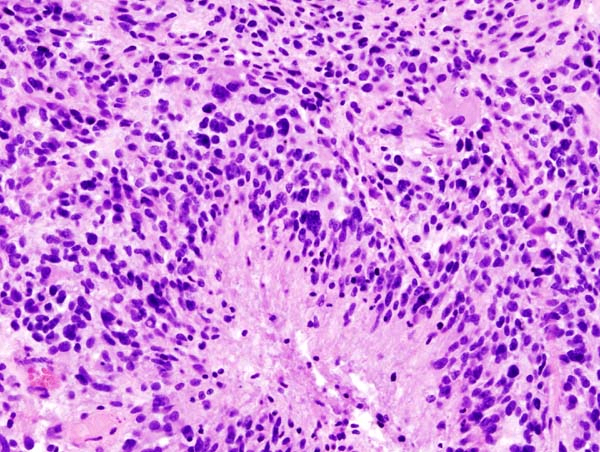

2) 병리소견

• 종양 세포는 과세포성(hypercellularity)을 띠며, 길게 늘어진 또는 불규칙한 과염색 핵을 가지며, 섬유질 배경(fibrillary background) 속에 위치

배경은 GFAP(교세포 섬유산성 단백질) 양성

Serpentine pattern의 괴사와 미세혈관 증식(microvascular proliferation)이 특징적

- 괴사 주변에 종양세포가 방사형으로 배열된 palisading necrosis 관찰됨

- 저산소증(hypoxia)에 반응하여 악성 성상세포가 VEGF를 분비 → 미세혈관 증식 유도